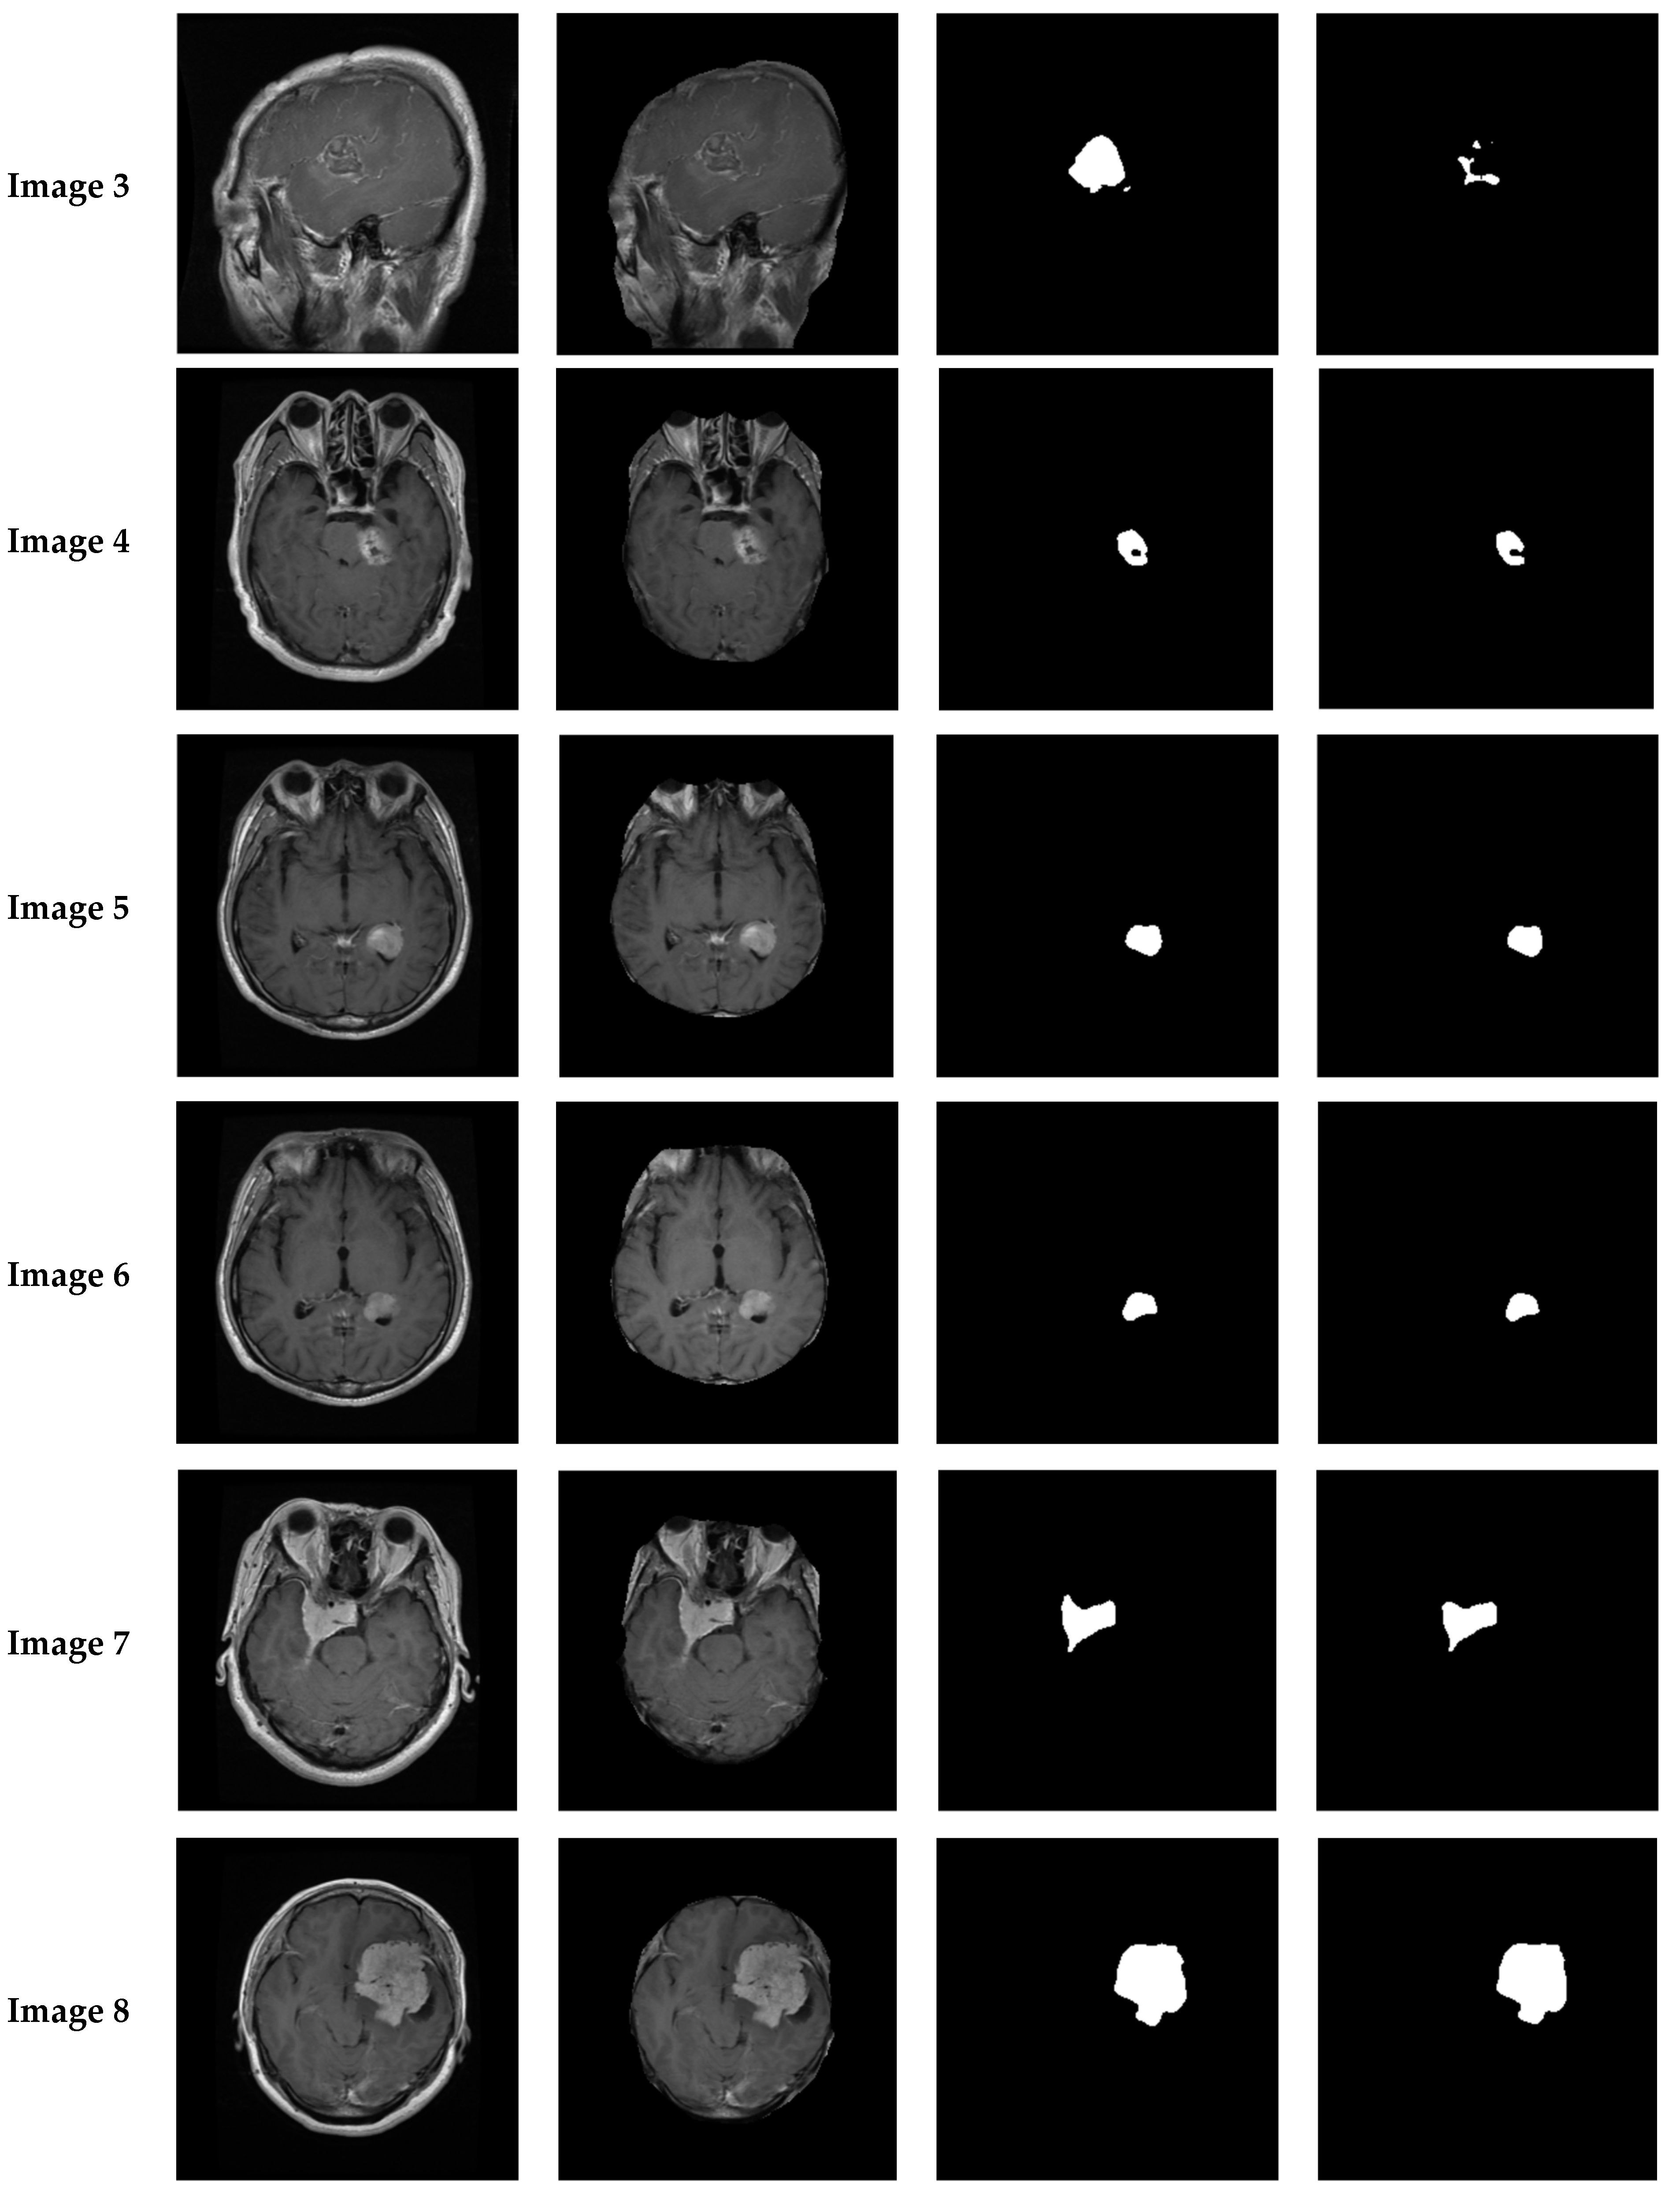

4.1.2. Experiments

- Experiment #1

- Experiment #2